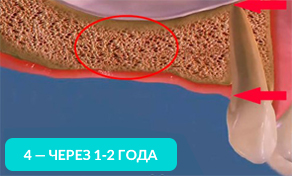

На 4-ом рисунке видно, что костная ткань стала значительно тоньше, теперь в это место уже невозможно установить импланты (потребуется операция по наращиванию костной ткани).

Обратите внимание, насколько тоньше стала кость на рисунке 4, как постепенно обнажается корень оставшегося зуба.

Убыль костной ткани распространяется на соседние зубы и их корни постепенно обнажаются!

Зубы, расположенные рядом с местом удаления, со временем становятся нестабильными и могут быть утрачены.